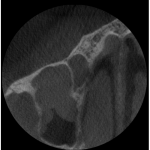

The CBCT (Cone Beam Computed Tomography) was instrumental in identifying multiple canals in this tooth. We knew from the conventional 2 dimensional radiograph that there were at least 2 roots/canals present. The CBCT showed 3 canals present. I was able to get access in all three canals and seal them.

A CBCT was not necessary to identify multiple roots in this lower 1st bicuspid but was able to help us identify the actual root configuration and to locate all three canals with relative ease and without over enlarging and weakening the per cervical dentin.

This was not my patient but this was shared to as an example of how dramatic the CBCT can show details in 3 dimensions vs. 2 dimensions. The photos speak for themselves.